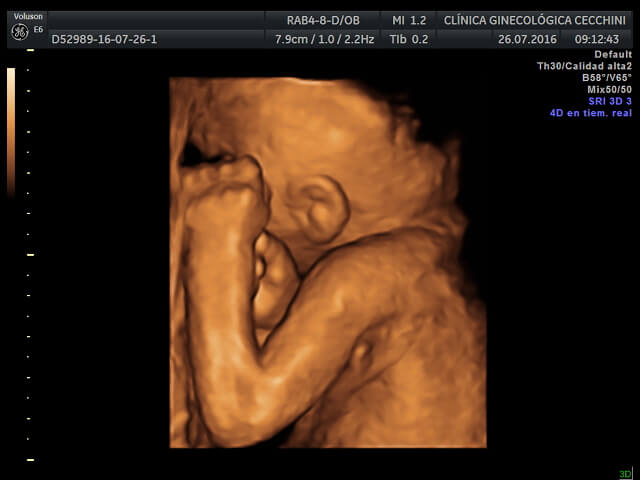

En la exploración ecográfica en 4D, debemos contar con la colaboración del feto, ya que en algunos casos está de espalda y es imposible ver su cara.